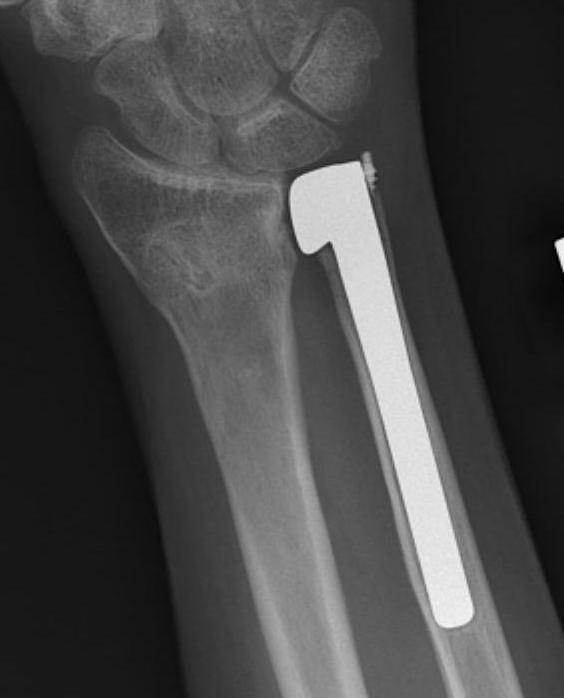

Suave-Kapanji distal radio-ulna arthrodesis

Technique

Distal radio-ulna arthrodesis with screws + proximal ulna pseudoarthrosis

- proximal ulna osteotomy and resection 1 cm to allow rotation

- debrided lateral ulna and sigmoid notch of radius

- radioulna arthrodesis with screws

- interposition with pronator quadratus to create proximal ulna pseudoarthrosis